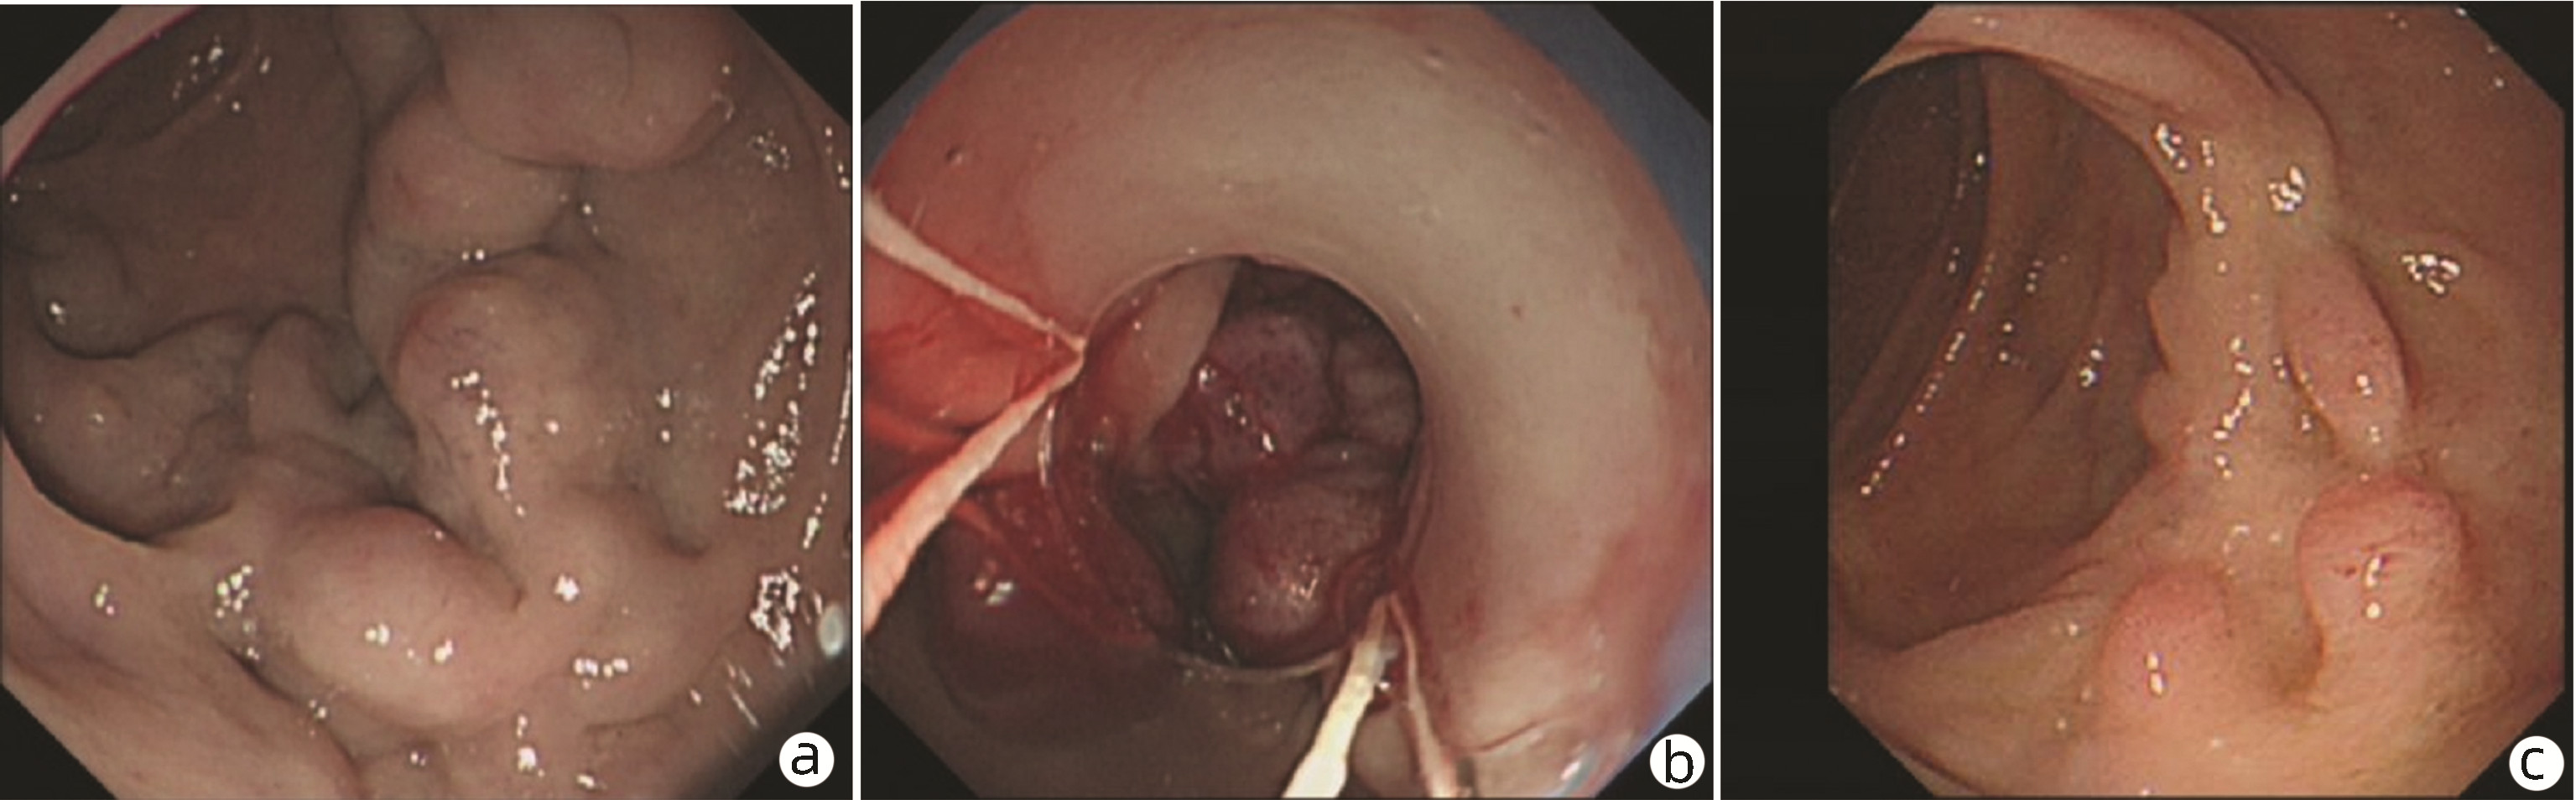

Endoscopic sequential ligation for treatment of esophageal and gastric varices with duodenal varices: A case report

Hao WEN, Zhaohui HE, Tong JIANG, Guoqing SHI

2023, 39(3): 637-639. DOI: 10.3969/j.issn.1001-5256.2023.03.024

Abstract(880) HTML (273) PDF (2676KB)(104)

Abstract: